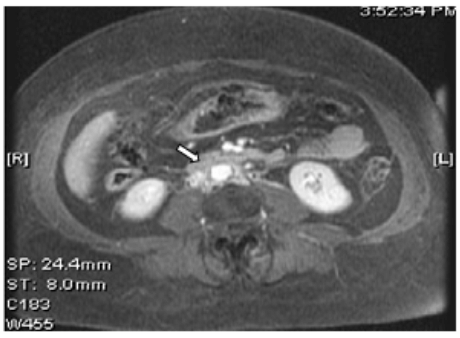

A 66-year-old African American female presented to the emergency department with a two months history of progressively decreasing urine output. She noticed no urine output for last one day. She had no history of chronic kidney disease, kidney stones or other significant medical illnesses in the past. She denied any abdominal pain, fever, chills or urinary tract symptoms. Her examination revealed blood pressure of 187/110 mmHg with 2+ pitting edema at ankles. A foley catheter was inserted in the emergency room but no urine output was recorded. Laboratory data showed serum creatinine of 9.2 mg/dl. Her serum creatinine was normal at 0.8 mg/dl, three months ago. A renal ultrasound showed normal sized kidneys with mild bilateral pelvicaliectasis. A non-contrast computed tomography (CT) scan of abdomen was unremarkable for stones but revealed mild hydronephrosis with indistinct periaortic fullness (Figure 1, arrow). Retrograde pyelogram revealed bilateral ureteral strictures. After placement of uretral stents, patient had brisk urine output and serum creatinine trended down back to the normal range. MRI with gadolinium done on day-3 of admission, showed an enhancing soft tissue infiltration encasing the abdominal aorta and IVC (Figure 2). No significant pelvic or retroperitoneal lymphadenopathy was identified. Fine needle aspiration biopsy of the retroperitoneal infiltration revealed metastatic adenocarcinoma in the background of dense fibrosis. The suspicion was raised for lungs, breast or uterus as the source of primary tumor. Patient's history was negative for any pulmonary, uterine or breast related symptoms. However, her breast examination that was deferred earlier on admission was suspicious for a left breast nodule. The mammogram revealed a 2x3 cm soft tissue density and an ultrasound guided fine needle aspiration biopsy confirmed the breast adenocarcinoma. The positive immunohistochemical staining of the malignant retroperitoneal tissue cells for estrogen, progesterone and herceptin-2 receptors, confirmed breast as the primary site. Patient was referred to oncology and she was initiated on palliative chemotherapy with weekly paclitaxel, carboplatin and herceptin. After six weeks of chemotherapy, patient was admitted with pneumonia, severe sepsis and respiratory failure. As per family and patient's prior wishes, she was made comfort care only and she expired two days after her hospitalization.

Figure 1: A non-contrast computerized tomography (CT) scan of abdomen shows mild hydronephrosis with indistinct periaortic fullness (arrow).